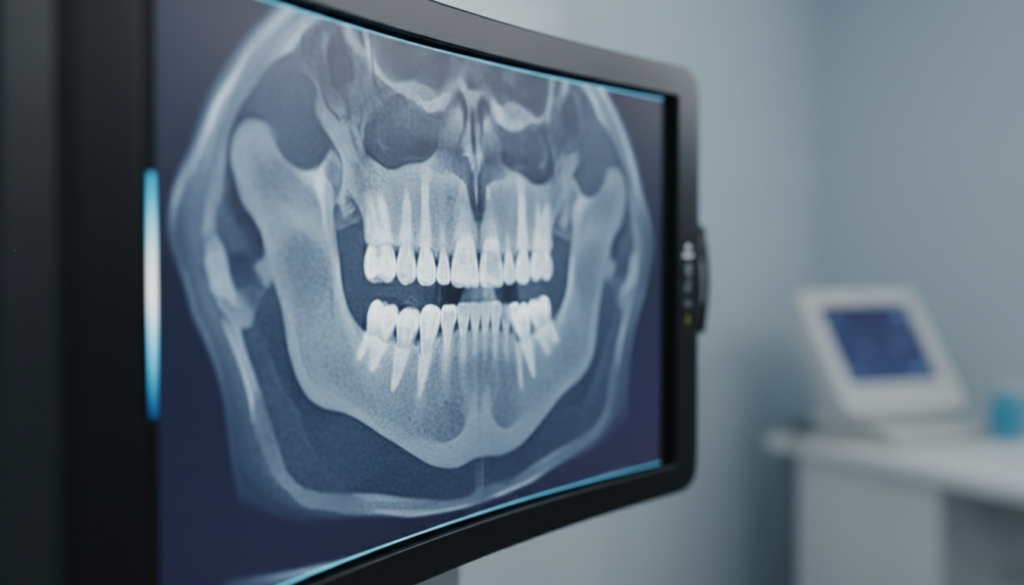

インプラント治療では、歯科用CTによる三次元診断が不可欠です。

CTスキャンにより、骨の厚み・高さ・密度、神経や血管の位置を正確に把握することができます。これらの情報をもとに、インプラントの埋入位置や角度、長さを綿密に計画します。

精密検査を行わずに治療を進めると、神経損傷や血管損傷などの重大な合併症を引き起こすリスクが高まります。安全な治療のためには、CTによる精密検査が必須です。